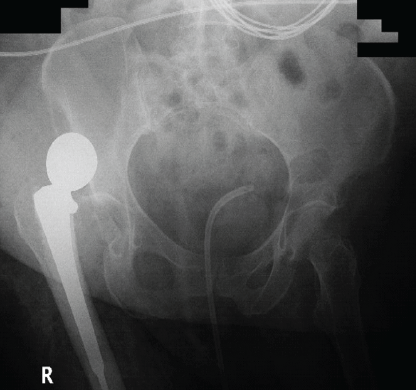

The patient returned to the ED due to an altered mental status, presenting with purulent drainage from a right hip wound. A shortened, painful, and internally rotated extremity was noted. Blood cultures grew Klebsiella. Imaging confirmed a posteriorly dislocated hemiarthroplasty (Fig. 3). The orthopedic team recommended open reduction with single-stage I&D and head-ball exchange due to the acute nature of the prosthetic joint infection (PJI) and chronic nature of the dislocation.

Figure 3: Anterior-posterior X-ray of initial posteriorly dislocated hemiarthroplasty.